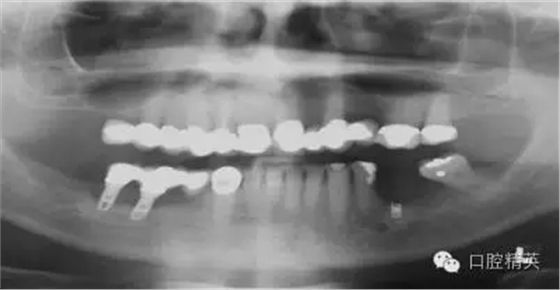

圖3a:術(shù)后的三維影像重建給外科醫(yī)生對(duì)手術(shù)入路的回顧以提示。對(duì)于這一病例進(jìn)行了Caldwell-Luc術(shù)式,用球鉆在上頜竇側(cè)壁做一窗口,直接入路取出種植體。

圖3b:醫(yī)生再來(lái)臨床觀察到的情況并不能準(zhǔn)確的反應(yīng)粘膜下牙槽骨的真實(shí)形態(tài)

圖3c:術(shù)前用ICAT椎體束CT成像診斷,斷層片顯示6,7號(hào)牙頰側(cè)牙槽骨根方凹陷,需要再種植體術(shù)中或術(shù)前植骨

另外一個(gè)棘手的問(wèn)題和上頜骨前部的解剖結(jié)構(gòu)有關(guān)。(圖3)這種病例,從臨床檢查上看,上頜骨量非常豐富,頜骨矢狀斷面呈三角形,符合Scott Ganz醫(yī)生所描述的“三角形骨”理論。這一理論幫助確定牙槽骨固有形態(tài),判斷最佳的種植體植入位置。

如這個(gè)病例展示的,CBCT斷層掃描揭示了牙槽骨根方的凹陷。這樣就避免了術(shù)中的意外,醫(yī)生可以在術(shù)前完善的計(jì)劃,向患者交代清楚手術(shù)方法、風(fēng)險(xiǎn)、以及植骨所需增加的相應(yīng)費(fèi)用等問(wèn)題。在兩維的放射影像中是無(wú)法預(yù)先觀察到這個(gè)問(wèn)題的。僅使用兩維放射診斷帶來(lái)的另一個(gè)并發(fā)癥是種植體折斷。(圖4)前面提過(guò),兩維曲面斷層影像難以獲得精確定位,有的醫(yī)生為了避免損傷下頜神經(jīng)管而應(yīng)用短種植體。這樣做的結(jié)果是增加了修復(fù)體-種植體長(zhǎng)度比,隨著時(shí)間的流逝會(huì)造成骨吸收,最終可能導(dǎo)致種植體折斷。